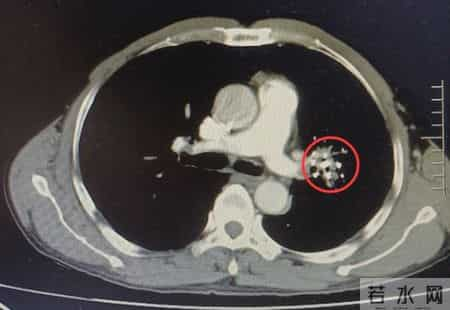

冠心病不是“突然发生”的这位男子的离世,并非一朝一夕的事。冠心病的形成,是几十年血管慢性损伤的结果。最初是内皮细胞受损,随后脂质沉积、斑块形成、血管狭窄。这些过程在无症状时已悄然发生,很多人第一次发作就是“猝死”。

更残酷的是,50%心梗患者在发作前从未被诊断出冠心病。他们以为自己“没症状就没病”,直到突然倒下。而吸烟,正是加速这一切的“催化剂”。